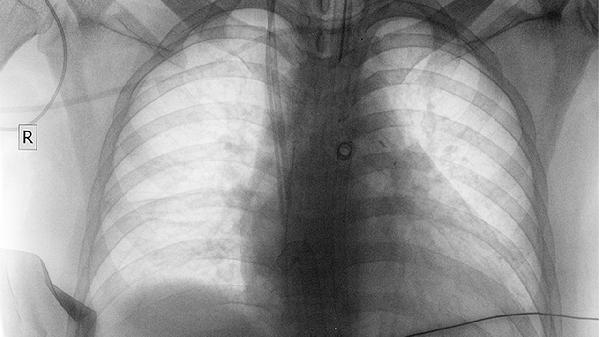

肺癌會引起咯血嗎

肺癌患者有可能會引起咯血,是因人而異的。有些患者不會出現(xiàn)咯血癥狀,但有些患者會出現(xiàn)輕微的咯血,或者是痰中帶血的情況,甚至會出現(xiàn)大咯血。主要是肺癌組織的血供比較豐富,當咳嗽時會導致毛細血管破裂出血,從而出現(xiàn)咯血的癥狀。所以,當出現(xiàn)肺癌時要進行及時的治療,特別是早期的肺癌,通過積極的手術治療,治愈率還是比較高的。但有一些晚期的肺癌,或者是身體不能耐受的患者,若不能進行手術治療,則可以選擇放療、化療或分子靶向藥物的治療,可以及時地緩解患者的癥狀,提高生存質量。